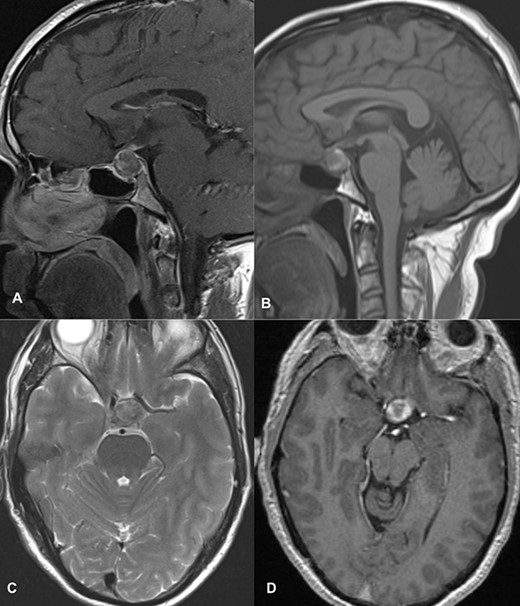

The patient underwent transsphenoidal pituitary adenectomy 3 days after admission. Intraoperatively, soft tumors with hemorrhagic components were seen. Hemostasis was achieved and the sella was packed with fat. The patient was managed in the ICU for 2 days and discharged on the 8th postoperative day. The ptosis gradually improved within 2 days of surgery, and during the 2-week follow-up in the outpatient clinic, the ptosis recovered completely. Follow-up imaging showed no evidence of a residual lesion in sella turcica (Fig. 4).

Follow-up imaging of case 2 showed no evidence of a residual lesion in sella turcica.